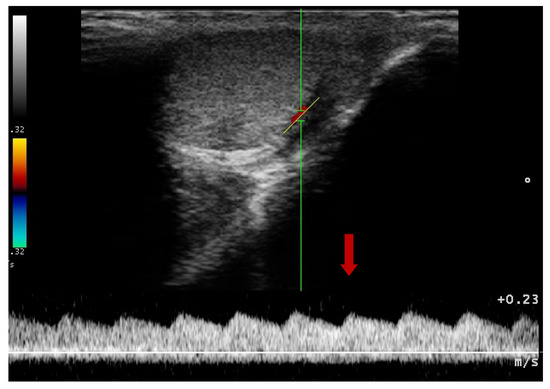

2.4. Doppler Ultrasonography—Prostate Gland

3.2. Doppler Ultrasonography of the Prostatic Artery